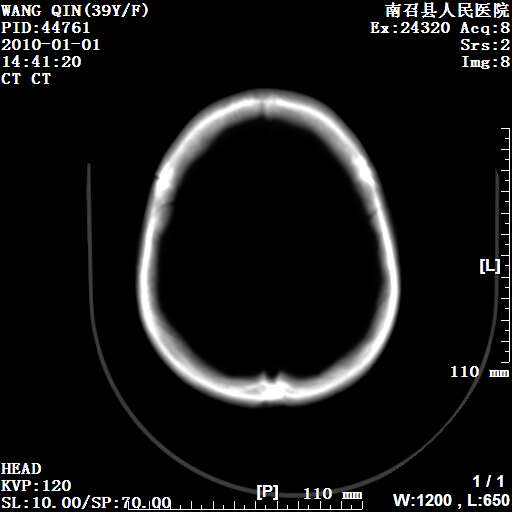

以下是引用随光逐影在2010-1-22 9:03:00的发言:[br]考虑左侧中颅窝(蝶骨翼区)脑膜瘤侵犯蝶骨翼并突入左侧眼眶。

以下是引用水过无痕在2010-1-22 14:55:00的发言:[br]一、定位:颅外占位;二、定性:恶性可能性大;三、组织来源:来源于左侧眼外直肌或其他部位;考虑为:横纹肌肉瘤>转移瘤>脑膜瘤.